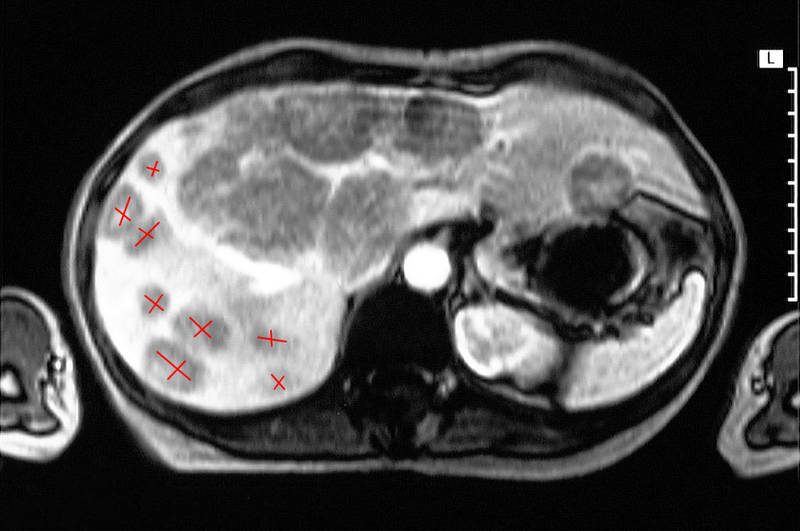

Распространение карциноида в печень, КТ-снимок

Клинические симптомы карциноида обусловлены как самой опухолью (частичная или полная непроходимость, кровотечения), так и выбросом в кровь большого количества серотонина и брадикинина. Приступы часто провоцируются приемом алкоголя, эмоциями и употреблением большого количества пищи, так как все эти факторы вызывают повышение уровня катехоламинов в крови. Классический карциноидный синдром наблюдается редко и появляется при метастазах карциноида в печень, так как в пораженной печени нарушается метаболизм серотонина печеночной моноаминоксидазой. Очень редко встречается так называемый атипичный карциноидный синдром с гиперинсулинизмом, гиперпродукцией АКТГ, гистамина и простагландинов.